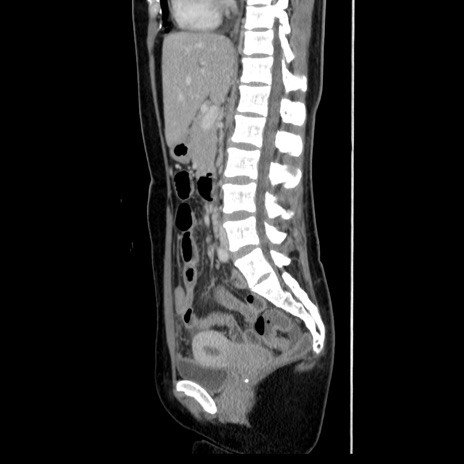

CT